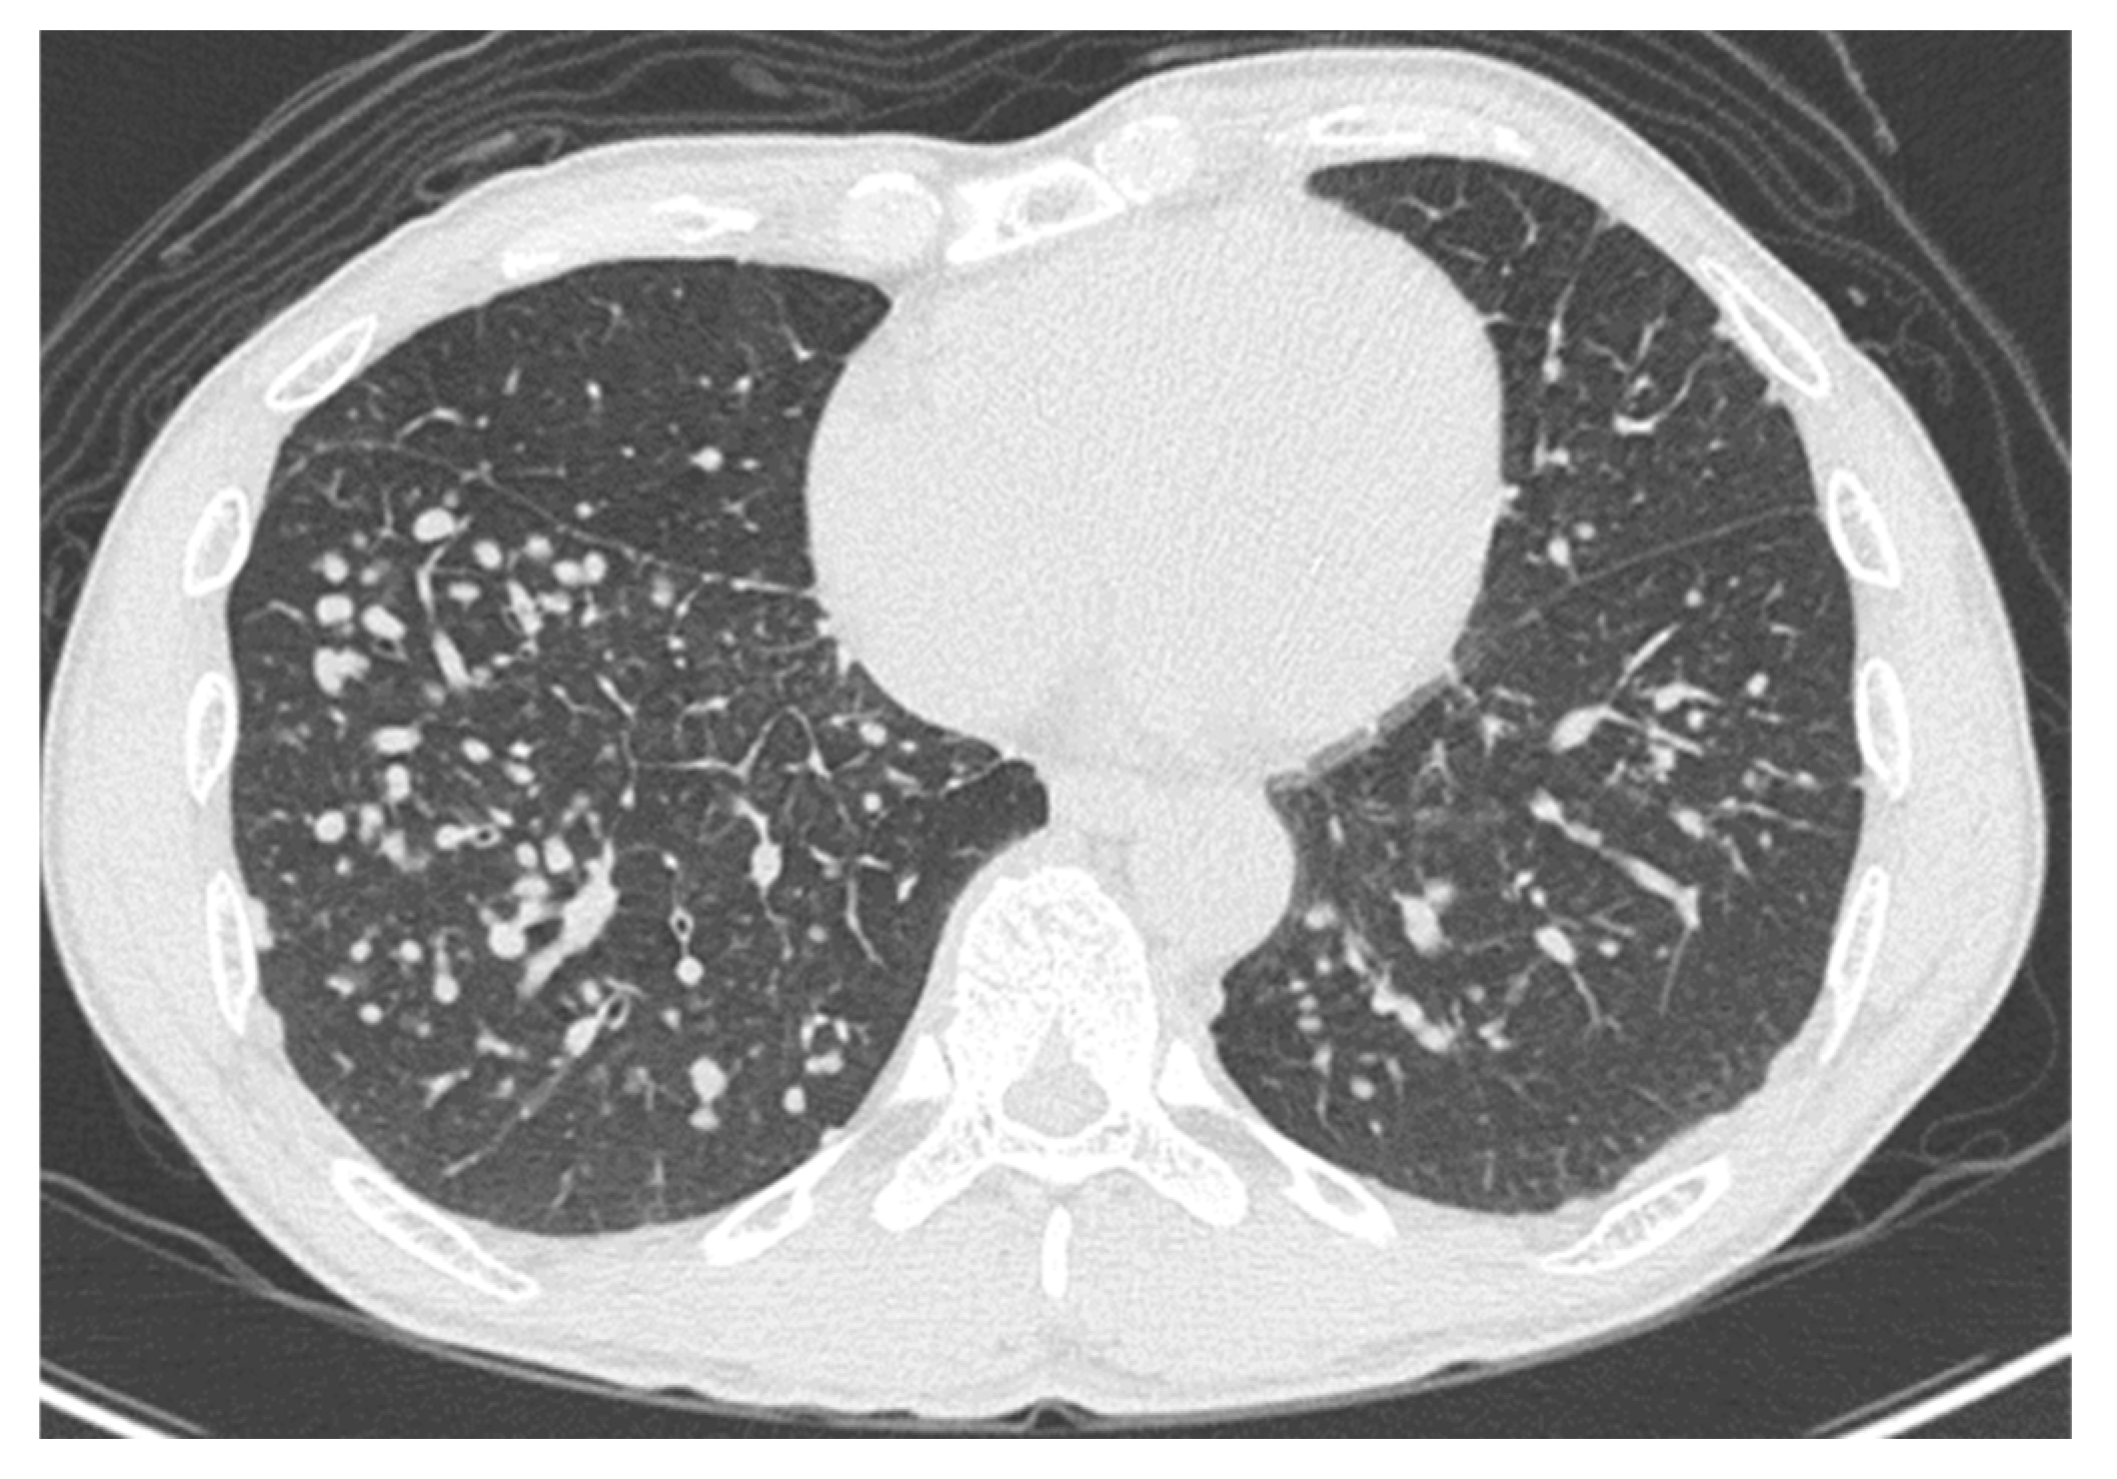

2. Case Presentation